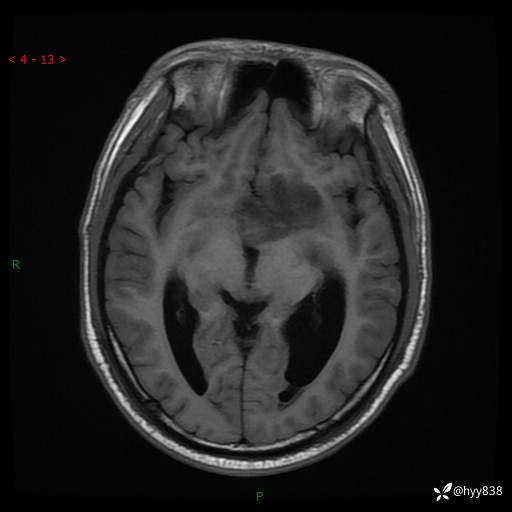

颅脑MRI平扫+增强